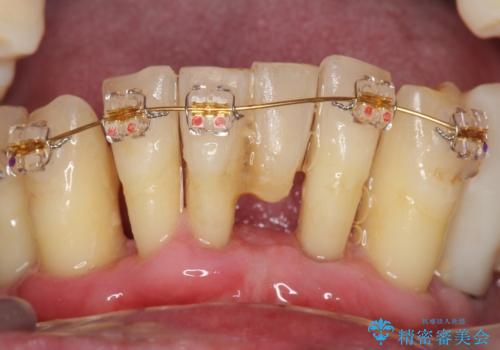

歯も神経も残したいという患者様のご希望により、補綴前に部分矯正を行っております。

補綴前に部分矯正を行うことで、歯の神経も保存することができました。

生活歯(神経が生きている歯)のため形成量(歯を削合できる量)に限界がありましたが、熟練の技工士さんの素晴らしい技術により補綴を行うことができました。